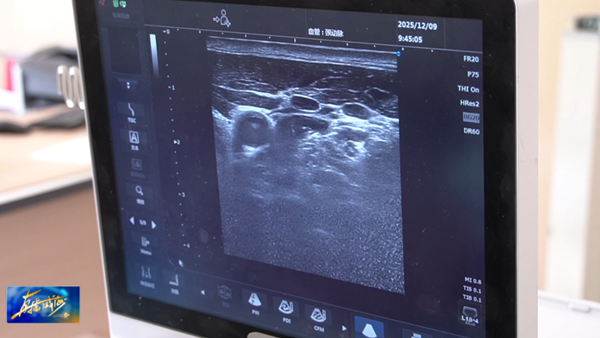

星状神经节是人体交感神经系统的“调节枢纽”,控制头颈部、上肢及胸部的血管收缩、汗腺分泌等功能。星状神经节阻滞,即在超声精准引导下,将少量麻醉药物注射至神经节周围,暂时抑制过度活跃的交感神经,恢复自主神经平衡,从而改善睡眠、缓解疼痛等。

威海市立医院麻醉科(睡眠门诊)副主任周业建说,自主神经功能已经受损了就像绷紧的皮筋无法松弛。整个神经一直处于绷紧的状态,正常人到晚上交感神经张力下降以后会进入快速入眠,这类睡眠不好的病人,大部分交感神经的张力非常高。不能靠自身调节把神经松弛下来,所以要借助神经调控技术。借助超声引导下星状神经节阻滞,是通过超声引导技术把局麻药,打到星状神经节周围,通过很少的药物把交感神经的调控开关松弛掉,达到神经调控的作用。

星状神经节阻滞仅需“发丝般细针”穿刺,全程采用超声可视化技术,可以避开血管、神经等器官,操作风险极低。与传统安眠药不同,星状神经节阻滞通过调节神经功能改善失眠症状,可以避免药物耐受性和成瘾风险。

威海市立医院麻醉科(睡眠门诊)副主任周业建说,借助超声技术之后,可以完整看到穿刺针在病人颈部完全的轨迹,可以精准扎到需要阻滞的部位达到神经阻滞的作用。神经调控只是把交感神经敏感性降到正常水平,不能把神经调控到低下的情况,不会影响患者正常的生活和工作。